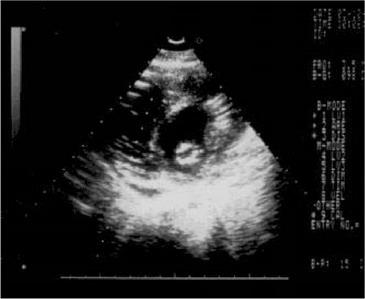

Эхокардиография (рис. 33):

- уменьшение экскурсии аорты. Рис. 33. Критический стеноз левого агриовентрику-лярного отверстия.

Рис. 33.

Критический стеноз левого агриовентрику-лярного отверстия.